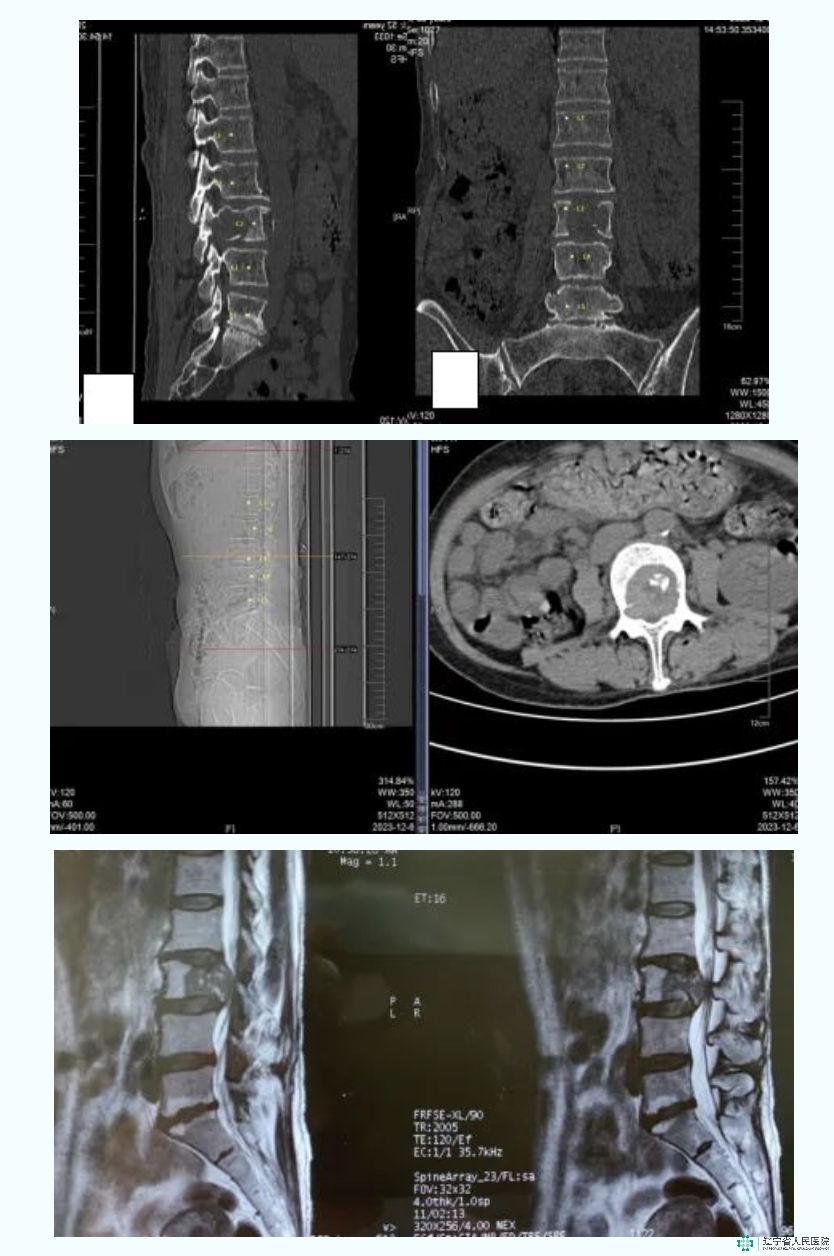

病例:高某某,女,58岁。诊断:腰3椎体转移瘤。Tomita评分:3分;SINS 评分:14分。采用分离手术腰3脊椎部分切除骨水泥占位内固定术。A-B-C:腰椎CT:矢状位、冠状位及轴位:可见腰3椎体溶骨性破坏;D-E:腰椎MRI矢状位及轴位:可见腰3椎体T2低信号改变,椎管内脊髓压迫显著,ESCC3级;F-G:腰椎正侧位DR:腰3椎体分离手术,术后改变。